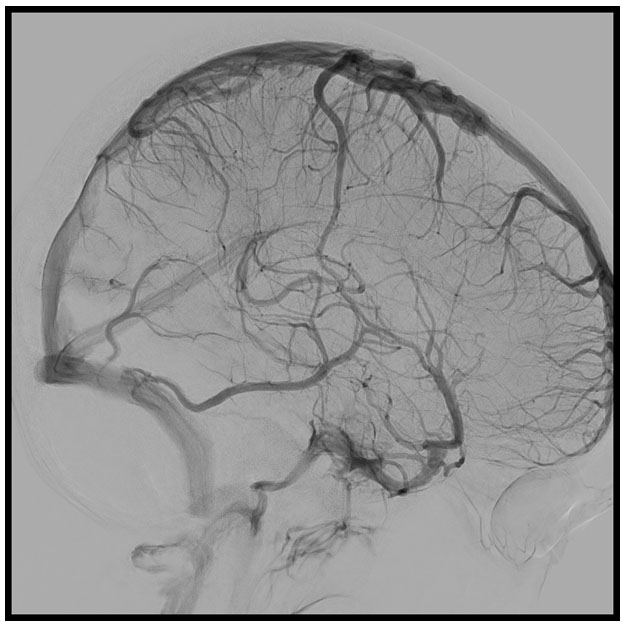

After checking the findings in the MRI, a selective angiography of both internal carotids and left vertebral arteries was performed (Figure 3). Arterial phase did not show intracranial hypervascularization or other relevant findings. Venous phase confirmed moderate and segmental stenosis of the posterior third of the superior sagittal sinus due to the meningioma, as well as slowed global intracranial cerebral venous circulation time, especially in relation to the cortical veins draining to the superior sagittal sinus. This finding was compatible with the suspicion of intracranial hypertension due to venous stasis.

Figure 3: Cerebral angiography of both carotid arteries and left vertebral artery in venous phase and sagittal projection, showing moderate and segmental stenosis of the distal third of the superior sagittal sinus due to the meningioma.

Share Image: